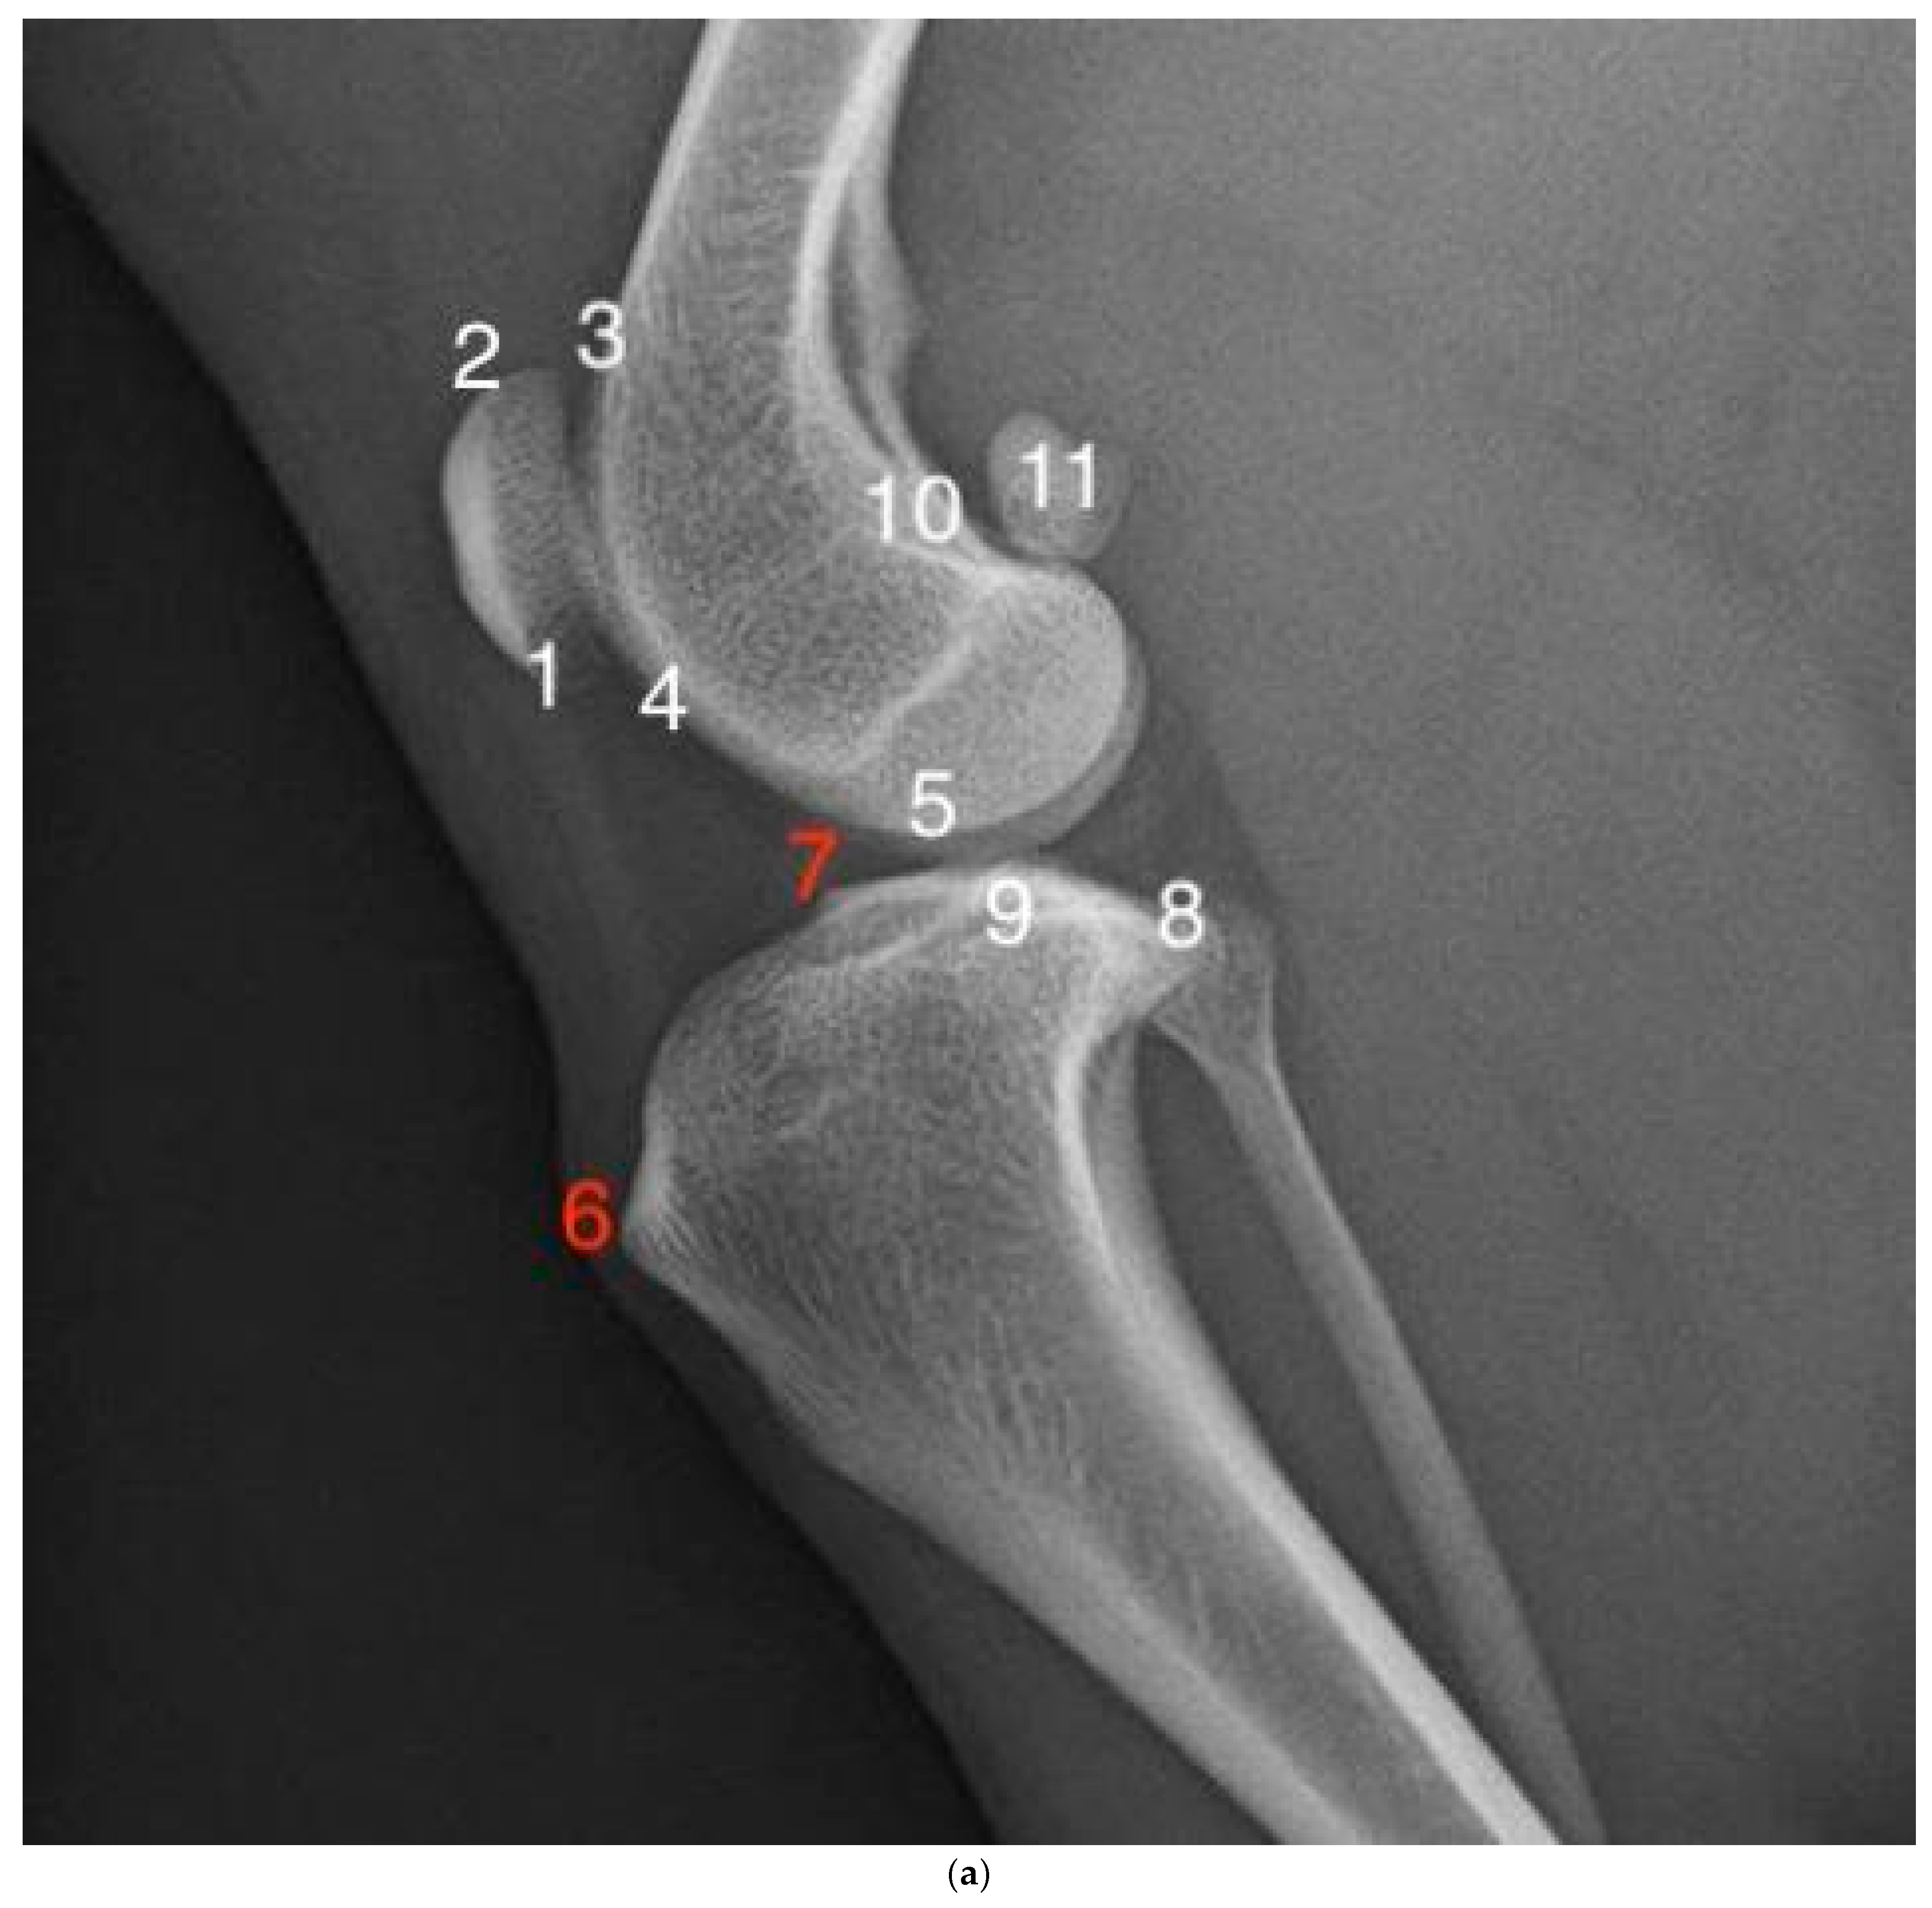

2.3. Radiographic Examination and Scoring